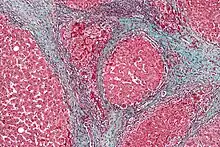

GAVE is characterized by dilated capillaries in the lamina propria with fibrin thrombi. The main histomorphologic differential diagnosis is portal hypertension, which is often apparent from clinical findings.

GAVE is usually diagnosed definitively by means of an endoscopic biopsy.[6][7][10][20] The tell-tale watermelon stripes show up during the endoscopy.[7]